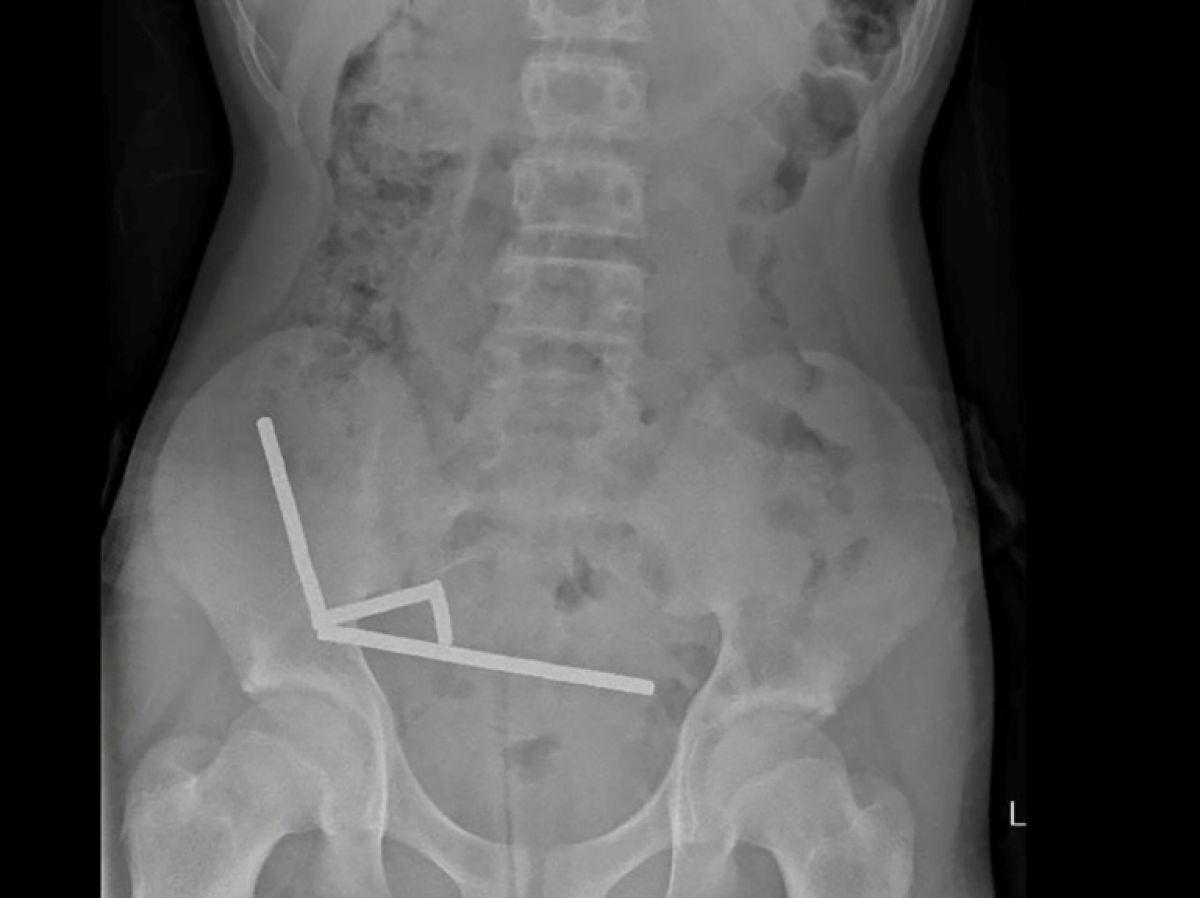

Africa-Press – Cameroun. Après avoir souffert de douleurs abdominales pendant quatre jours, l’adolescent a été transporté à l’hôpital de Tauranga, sur l’île du Nord. « Il a avoué avoir ingéré entre 80 et 100 aimants puissants au néodyme, de 5x2mm environ, une semaine plus tôt », indique un rapport des médecins de l’hôpital de cet hôpital, publié dans le New Zealand Medical Journal (NZMJ).

Ce type d’aimants, interdit en Nouvelle-Zélande depuis janvier 2013, aurait été acheté sur la plateforme chinoise d’e-commerce Temu. Les médecins ont déclaré que la pression exercée par les aimants avait provoqué une nécrose dans quatre zones de l’intestin grêle et du gros intestin du garçon.

Il a été opéré afin que l’on lui retire les aimants et les tissus nécrosés, et il a pu rentrer chez lui après huit jours à l’hôpital. L’article explique qu’une intervention chirurgicale à la suite de l’ingestion d’aimants peut entraîner des complications, telles qu’une obstruction intestinale, une hernie abdominale et des douleurs chroniques.